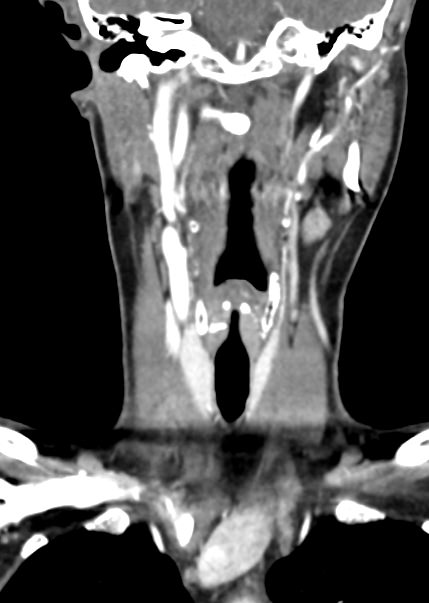

Оптимальным методом обследования гортани и голосовых связок является мультиспиральная компьютерная томография. Метод позволяет подробно визуализировать состояние данной анатомической области и выявить патологические изменения, которые незаметны при ларингоскопии (визуальный осмотр гортани с помощью специальных инструментов), проведении УЗИ и обычной рентгенографии.

Компьютерная томография позволяет оценить состояние костного скелета гортани и особенно важна в оценке состояния хрящей гортани, которые лучше всего визуализируются с помощью данного исследования. В частности, мультиспиральная КТ позволяет выявить распространение рака гортани в ткань щитовидного хряща и другие окружающие структуры.

При подозрении на опухоль гортани нативная мультиспиральная КТ дополняется проведением внутривенного болюсного контрастирования. Для этого пациенту внутривенно вводится контрастный препарат на основе йода.

Контраст хорошо накапливается в патологически измененных участках, за счет этого становятся отчетливо видны на снимках их границы, размеры, точная локализация относительно окружающих здоровых тканей. По характеру накопления контраста можно отличить доброкачественные опухоли от злокачественных, определить степень распространенности процесса, выявить поражение регионарных лимфатических узлов.

На полученных снимках можно оценить состояние всех структурных элементов гортани, голосовых складок, хрящей, а также лимфатических узлов, сосудов и шейных позвонков на исследуемом уровне. Инновационные возможности аппаратов позволяют построить 3D-модель зоны исследования, которая дает наглядную картину пространственного расположения органов, что бывает особенно важно при планировании хирургических операций.